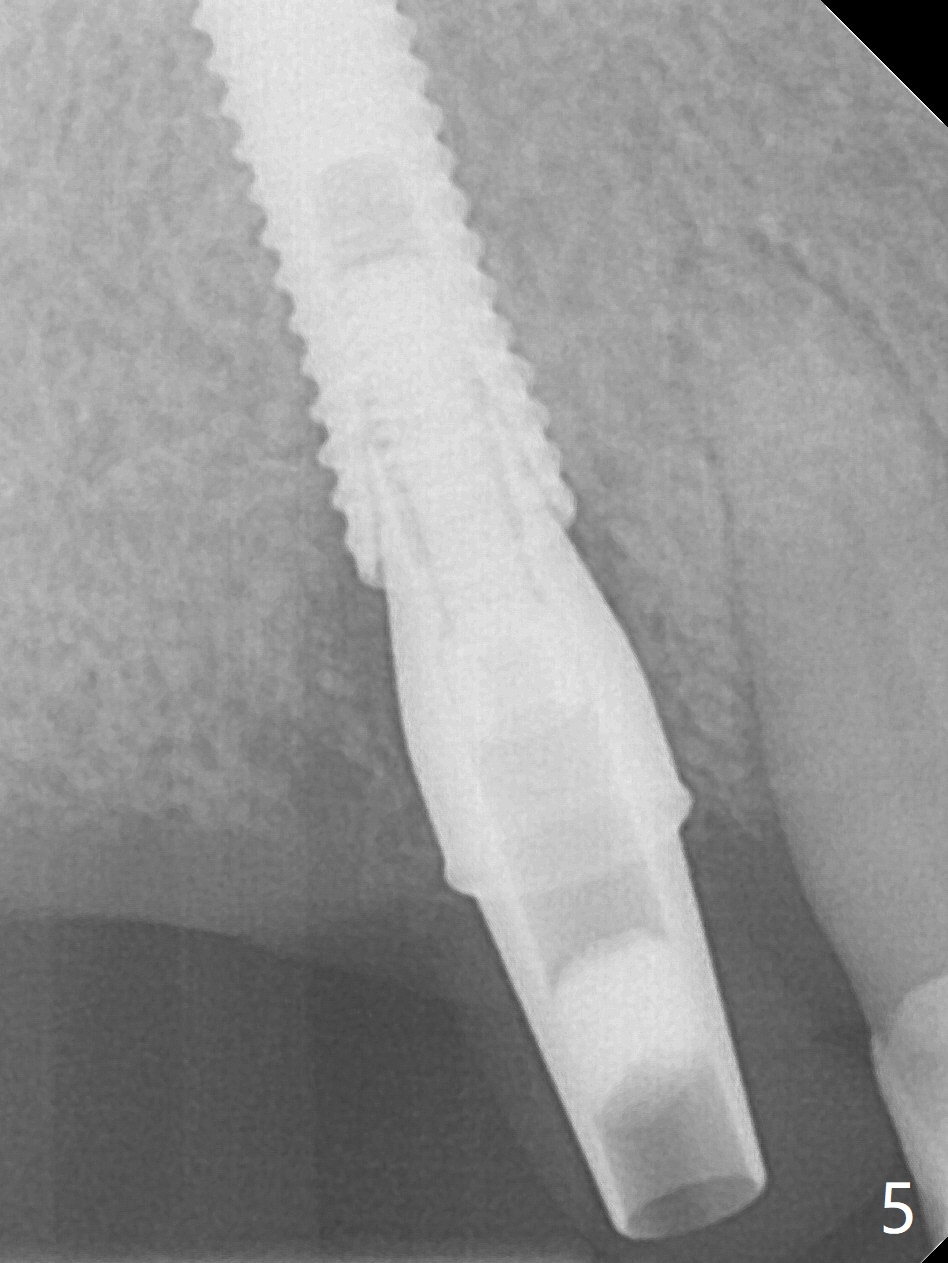

Extraction of the tooth #5 with mobility III reveals no buccal plate and low palatal plate.  Osteotomy starts as palatal as possible (Fig.1).  The bone density is low.  After use of 2.7 mm drill (Fig.2), a 3 mm drill can be inserted into the osteotomy without resistance.  A 4x16 mm implant is placed with insertion torque <30 Ncm.  When an abutment is placed, the implant is found to have been placed distal.   The implant is untorqued for change in trajectory.  When a 4.5x7(5) mm abutment is placed, the abutment turns with the underlying implant (Fig.3).  The former is kept to be turned with a hand driver until the latter is unable to turn.  Following placement of allograft (Fi.g3,4 *), a mini-provisional is fabricated to retain the bone graft and at the same time not to be interfered with when a flipper is in and out.  The bone graft in the former socket gap appears to have integrated into the native one 4.5 months postop (Fig.5).